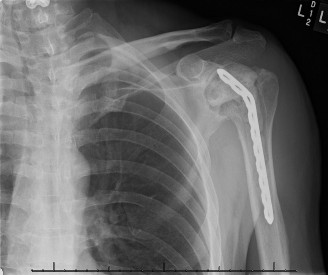

- Plain Radiographs: AP, scapular Y, axillary views. Assess for loosening, osteolysis, component migration, stress shielding, or heterotopic ossification. Baseline films are crucial for comparison.

Figure 3: Post-operative image, possibly a plain radiograph showing the definitive implant in place after successful two-stage revision for TSA PJI, with good component alignment.